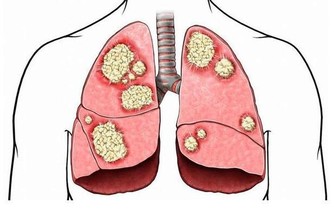

因為肝臟是唯一沒有痛感神經的器官,所以無論它累成怎麼樣,它也從不呻吟叫苦,也不會喊痛,這也是人們經常忽略它健康狀況的根本原因。這就是為什麼肝癌一發現,就是晚期的原因。

肝臟其實是一個非常重要的髒器,它掌管著糖、脂肪、蛋白質的解毒、代謝,人體大部分的新陳代謝和有毒物質的轉化,因此,它也是最易污染的部門。

肝臟“罷工”潛伏期長,病情隱蔽,尤其是中早期,往往症狀不明顯,再加上人們意識不足,治療極易被延誤。